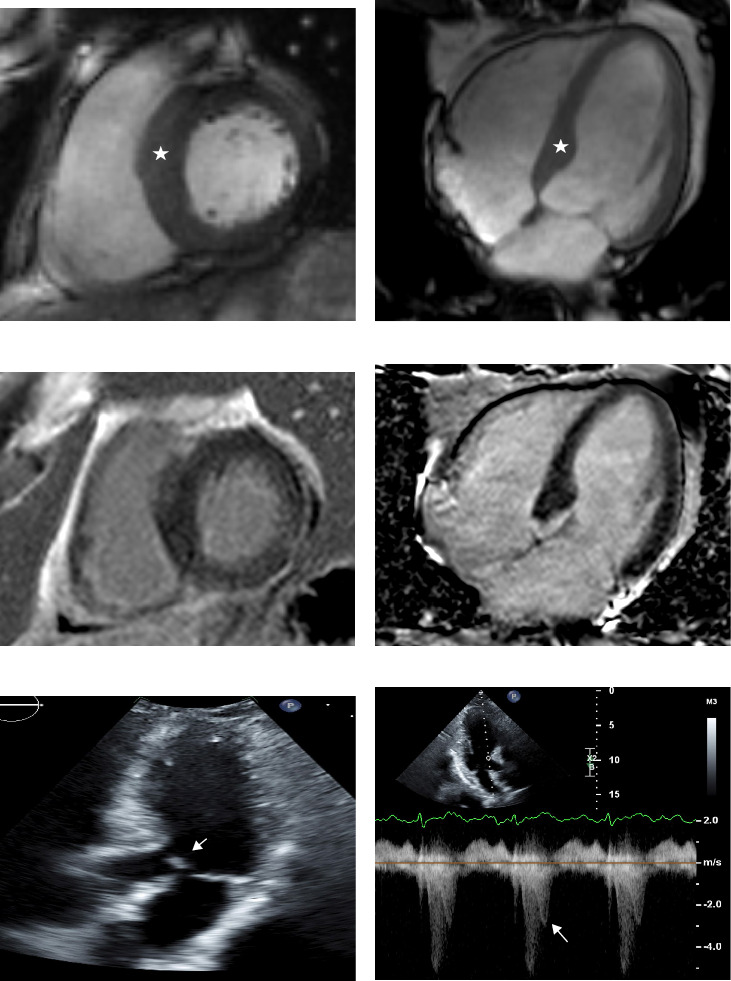

Acromegaly is a rare disease that is caused by a growth hormone (GH) secreting pituitary tumor. This is a case of a 62-year-old man who presented with hypertrophic cardiomyopathy more than 25 years after surgical remission without other known etiologies of left ventricular hypertrophy. The patient initially presented at age 28 with symptoms of acromegaly and diagnosed himself, while several physicians dismissed the diagnosis. He underwent transsphenoidal surgery associated with long-term remission. At age 53, he developed palpitations, light headedness, dizziness, and chest tightness, and an echocardiogram demonstrated left ventricular hypertrophy. At age 60, cardiac magnetic resonance imaging (MRI) suggested hypertrophic cardiomyopathy, which continues to be followed. This case raises the question of whether cardiac morphological changes occur in patients with acromegaly who have GH and insulin-like growth factor-1 (IGF-1) levels well controlled. Cardiac MRI is the most accurate imaging modality for assessment of cardiomyopathy. However, more research is needed to inform clinical guidelines on screening for cardiac functional and morphological changes in patients with acromegaly.

Abstract Image